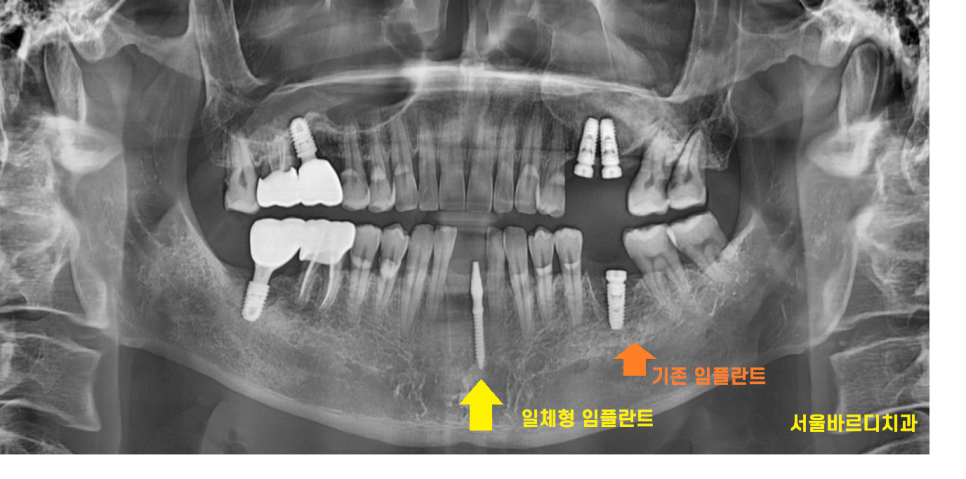

23.06.16

기존 임플란트와 비교해보았을 때

차이가 나는게 딱 보이죠~!?